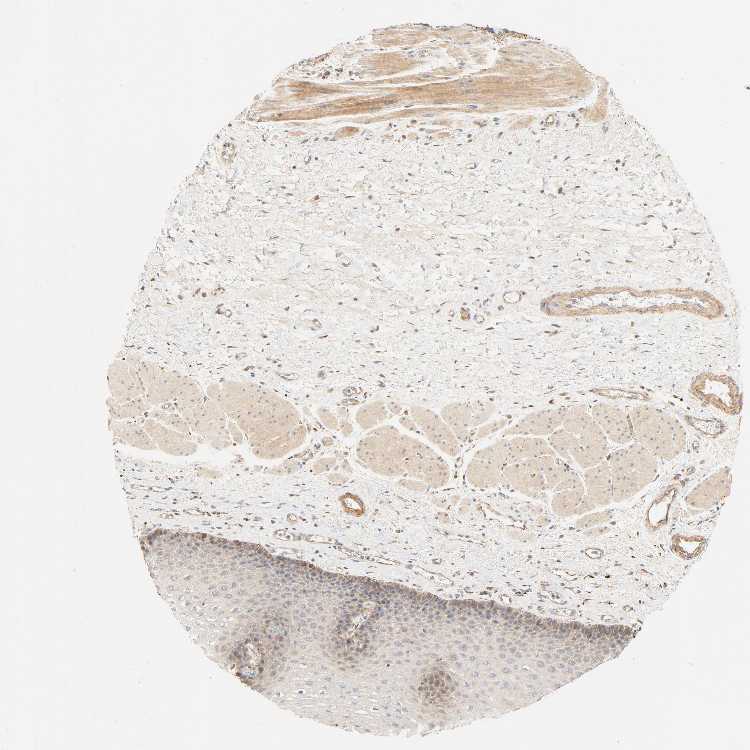

ESOPHAGUS - Antibody stainingi

Antibody staining in the annotated cell types in the current human tissue is reported as not detected, low, medium, or high, based on conventional immunohistochemistry profiling in selected tissues. This score is based on the combination of the staining intensity and fraction of stained cells.

Each image is clickable and will lead to virtual microscopy that enables deeper exploration of all samples and also displays staining intensity scores, fraction scores and subcellular localization as well as patient and tissue information for each sample.

Antibody HPA030262Antibody HPA047825Antibody CAB005184

Squamous epithelial cells MediumMediumMedium